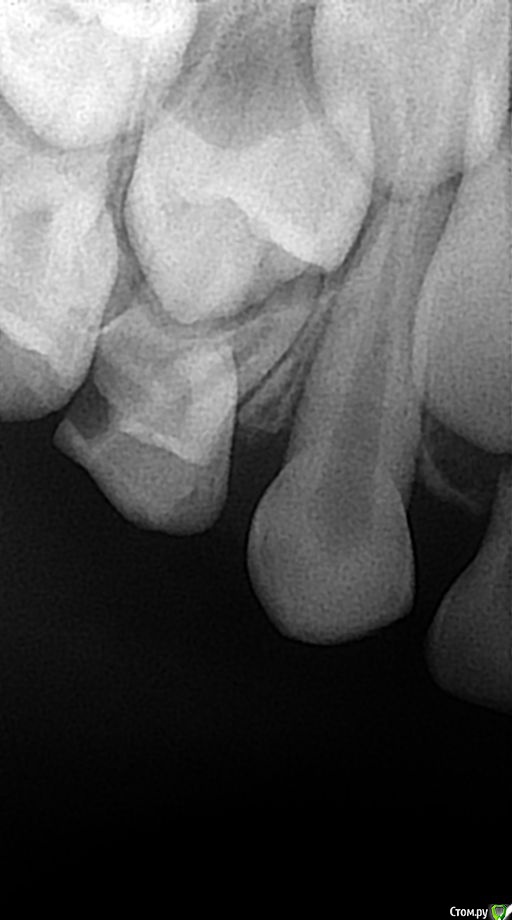

alin8888 Опубликовано 6 января, 2018 Автор Поделиться Опубликовано 6 января, 2018 Что объяснить?Мы ситуацию только с Ваших слов видим. Давайте снимки до и после, тогда уже будем понимать о чём идёт речь.Для того, чтобы не было смещения зубов на место удаленного, обратитесь к ортодонту, профилактические конструкции легко переносятся детьми.снимки есть, один сделан до удаления, другой после.Какой до, какой после не понимаю. Но мне еще раз сегодня сказали, что если уже пошло восполнение,которое проявилось в виде опухшей щеки ,восполненных десен- удаление . Ссылка на комментарий

alin8888 Опубликовано 6 января, 2018 Автор Поделиться Опубликовано 6 января, 2018 (изменено) второй снимок Изменено 6 января, 2018 пользователем alin8888 Ссылка на комментарий

alin8888 Опубликовано 7 января, 2018 Автор Поделиться Опубликовано 7 января, 2018 хотелось бы получить ответ из данных снимков.спасибо Ссылка на комментарий

сирена Опубликовано 7 января, 2018 Поделиться Опубликовано 7 января, 2018 Вам же дали ответ:мезиальный корень остался,со временем "выползет" на поверхность,можно будет его атравматично удалить.Если другие врачи не пишут,значит добавить нечего.У нас ответы на вопросы пациентов - дело добровольное. 1 Ссылка на комментарий

alin8888 Опубликовано 7 января, 2018 Автор Поделиться Опубликовано 7 января, 2018 насчет корня понятно. По снимкам действительно, только удаление? Отправила снимки,чтобы не было только с моих слов... Ссылка на комментарий

Brigita Опубликовано 7 января, 2018 Поделиться Опубликовано 7 января, 2018 Да, только удаление. Врач сделал все верно. 2 Ссылка на комментарий